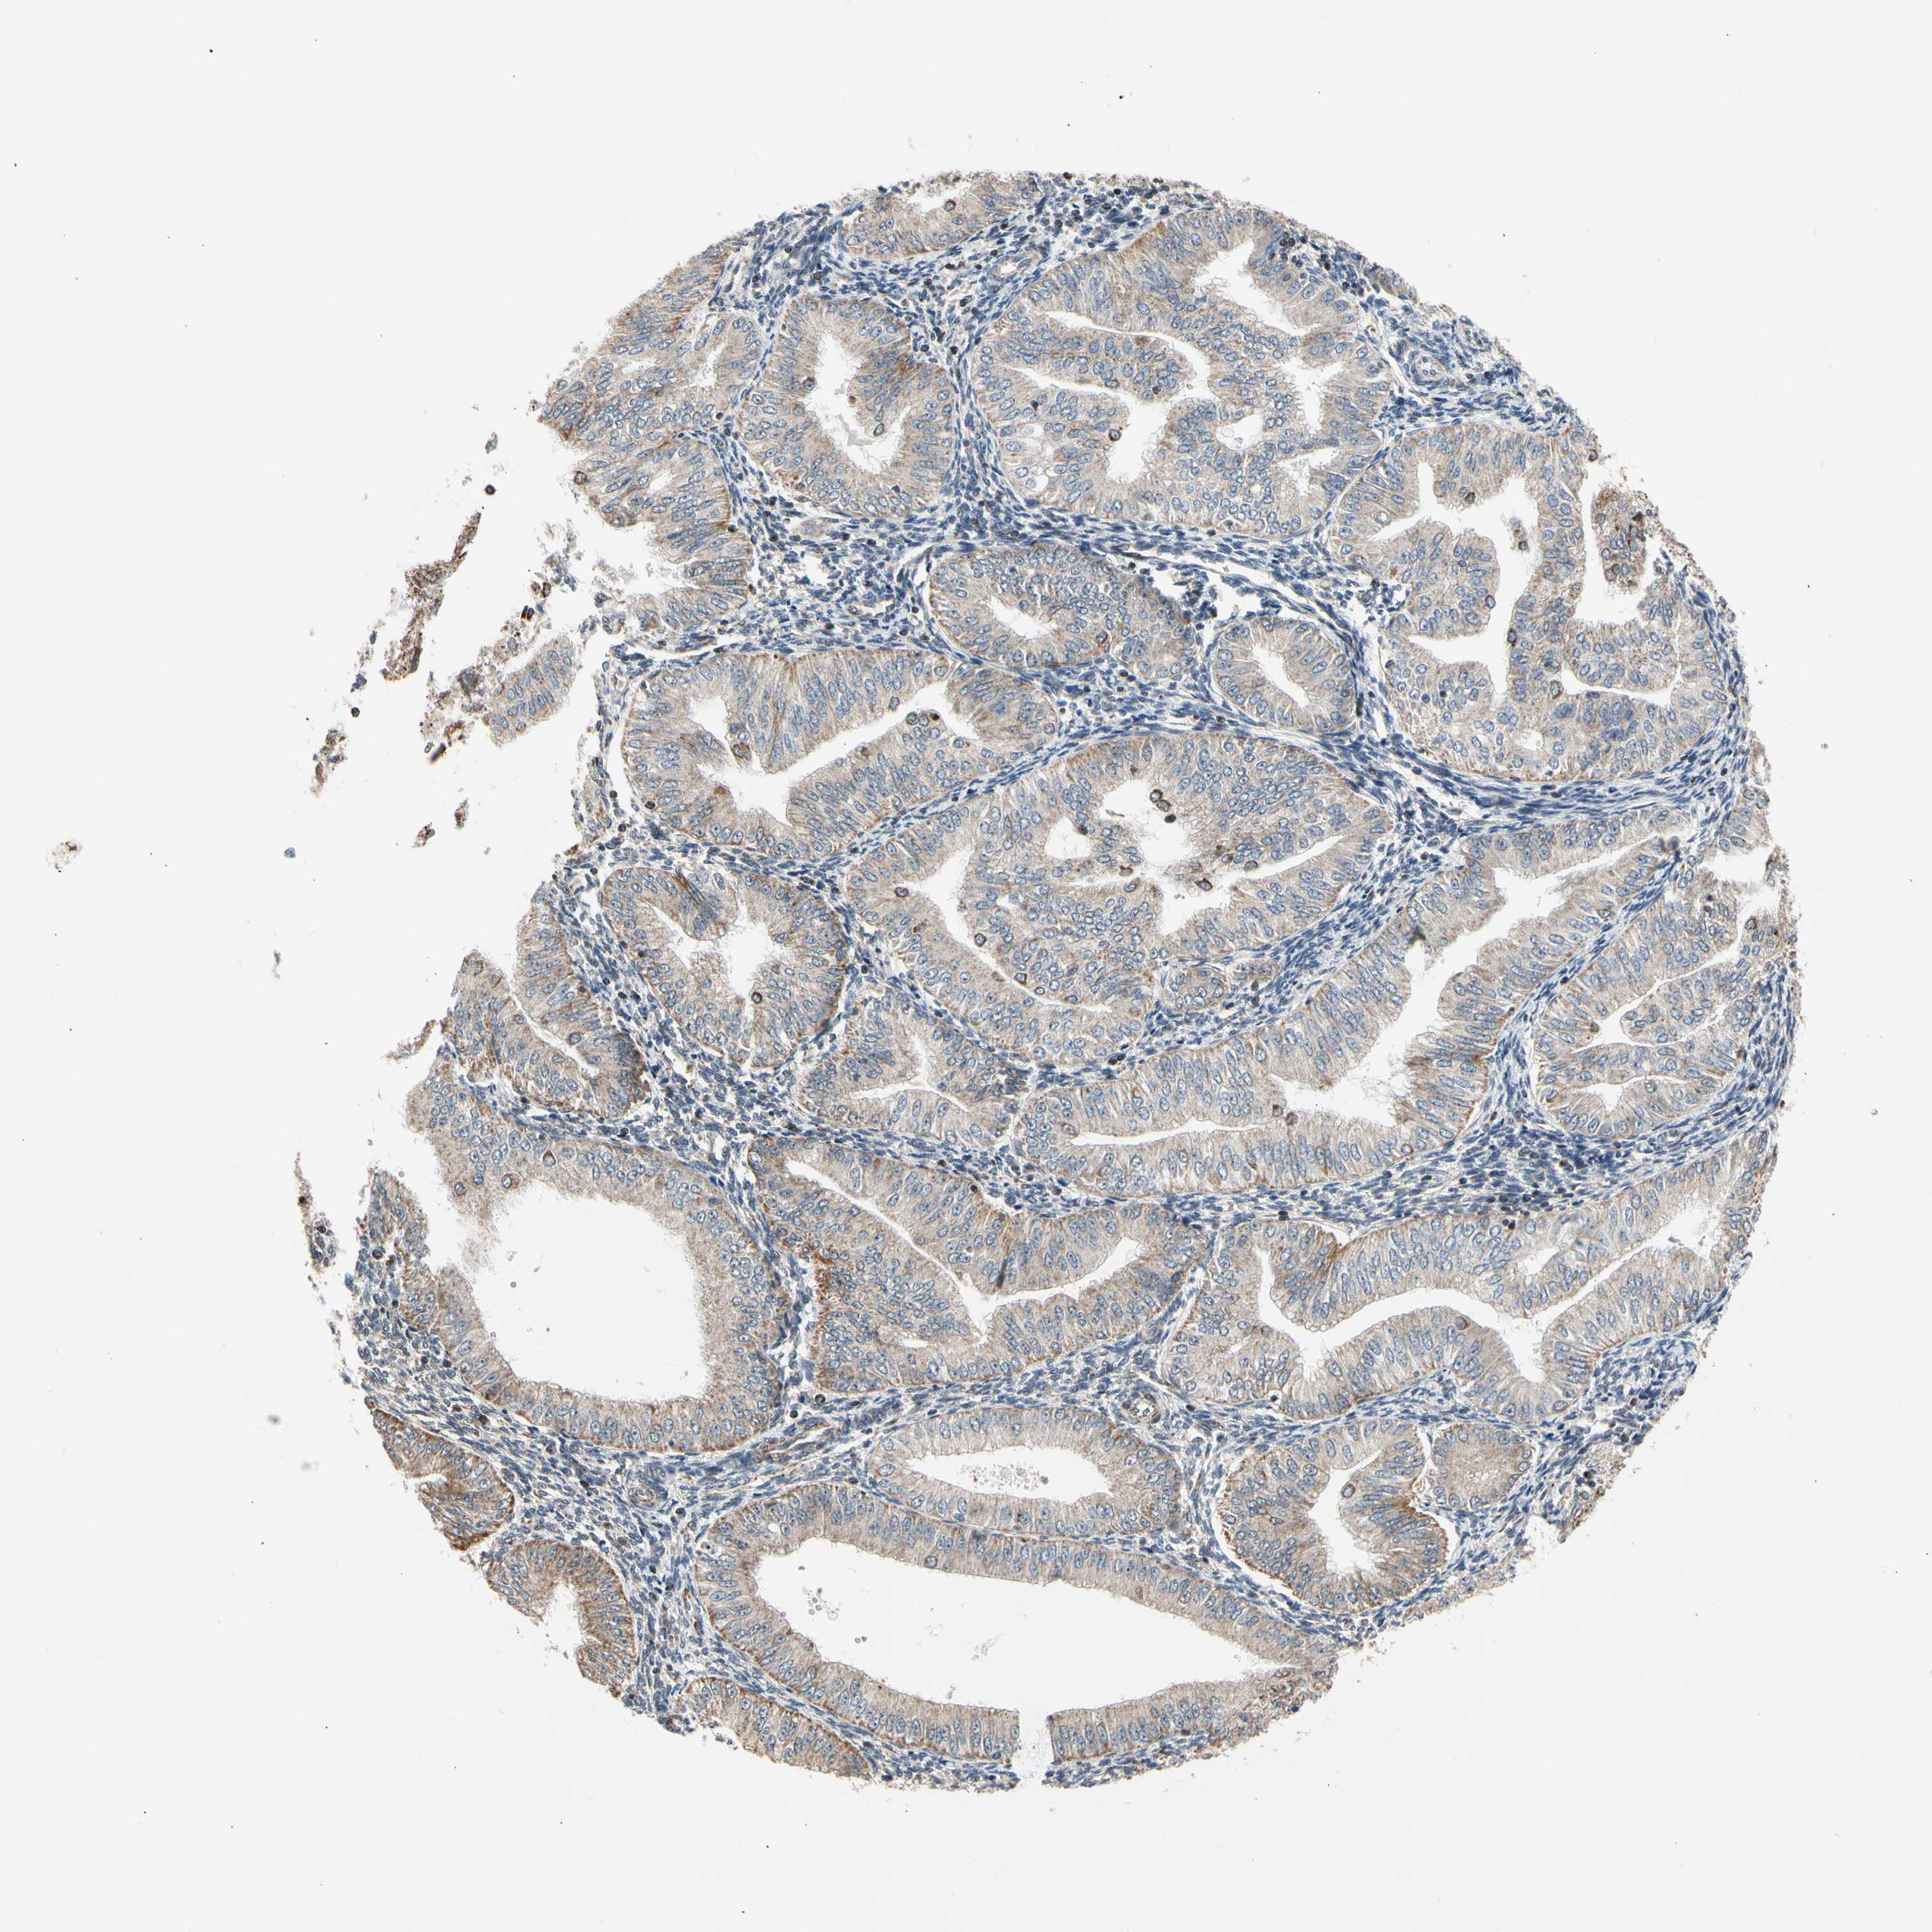

ENDOMETRIAL CANCER - Protein expressioni

A mouse-over function shows sample information and annotation data. Click on an image to view it in a full screen mode. Samples can be filtered based on level of antibody staining by selecting one or several of the following categories: high, medium, low and not detected. The assay and annotation is described here.

Note that samples used for immunohistochemistry by the Human Protein Atlas do not correspond to samples in the TCGA dataset.

Antibody stainingi

Antibody staining in the annotated cell types in the current human tissue is reported as not detected, low, medium, or high, based on conventional immunohistochemistry profiling in selected tissues. This score is based on the combination of the staining intensity and fraction of stained cells.

Each image is clickable and will lead to virtual microscopy that enables deeper exploration of all samples and also displays staining intensity scores, fraction scores and subcellular localization as well as patient and tissue information for each sample.

Antibody HPA008796

Staining

High

Medium

Low

Not detected

Intensity

Strong

Moderate

Weak

Negative

Quantity

>75%

75%-25%

<25%

None

Location

Nuclear

Cytoplasmic/membranous

Cytoplasmic/membranous,nuclear

Adenocarcinoma, NOS